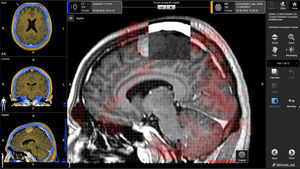

... configurado. Análisis longitudinal cerebral por RM (LOBI) El Análisis Longitudinal del Cerebro por RM destaca los cambios neurológicos sutiles a lo largo del tiempo. La aplicación admite ahora la generación de series FLAIR*. ...

... El software MeVis realiza análisis complejos basados en imágenes para enfermedades neurológicas, proporcionando así una base para una planificación segura y conservadora de la cirugía cerebral. fMRI-(imágenes ...

software de análisis de imágenesBrainance MD

Con Brainance MD puede crear informes de examen que incluyan todos los hallazgos del análisis de los exámenes de RM cerebral, como capturas de pantalla, mapas y anotaciones. El informe se genera automáticamente con sólo pulsar un botón ...

... Nuestras revolucionarias herramientas de neuroimagen se integran a la perfección en sus flujos de trabajo clínicos diarios de TC y RM para ayudarle en cada paso de la toma de decisiones en entornos previos y posteriores al tratamiento. Diagnóstico ...